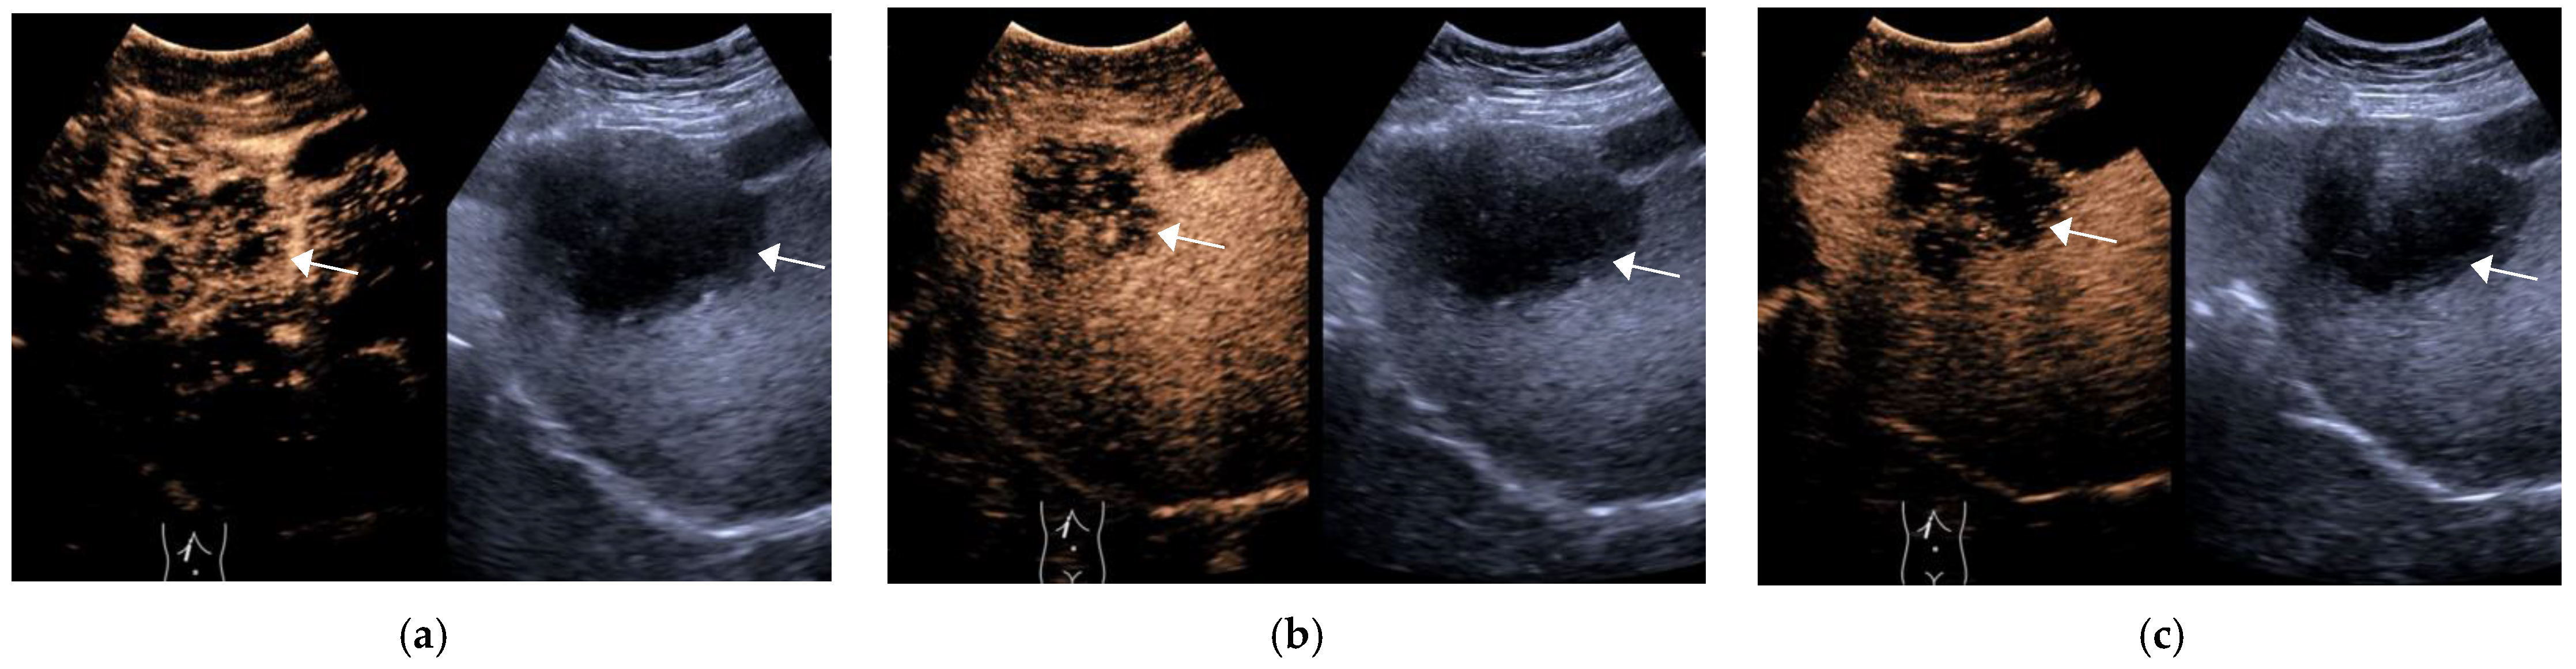

Figure 4.

Male, 54 years old, LR-M Category. A hypoechoic lesion (arrow), approximately 5.2 × 5.1 cm in size, is seen in LR-M liver S5, with inhomogeneous hyperenhancement at 23 s in the arterial phase (a), starting to wash out at 65 s in the portal phase (b) and significantly wash out at 144 s in the delayed phase (c). The final pathological diagnosis was combined hepatocellular carcinoma and cholangiocarcinoma. (The white line on the right represents the focus point of the image.)